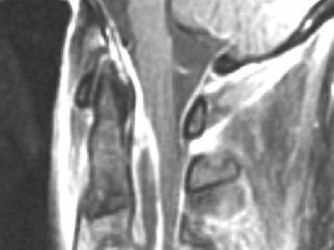

CASE 1 A 63-year-old male sustained a hyperextension injury to his neck while diving into a pool. Upon presentation, he reports decreased sensation in his hands and decreased strength in his arms and wrists, but no lower extremity complaints. On motor examination, he has 5/5 strength in his deltoids and elbow flexors and 4/5 strength in the elbow extensors, wrist extensors, and finger flexors. Lower extremity motor examination is normal. Sensation is decreased to light touch in both hands. Otherwise his sensation is preserved. Images of his cervical spine are shown in Figures 1–1 to 1–3.

Figure 1–1

The correct answer is (B). The clinical scenario describes a patient with central cord syndrome (CCS). CCS continues to be the most common incomplete spinal cord injury accounting for 15.7% to 25% of all spinal cord injuries. The characteristic presentation is an extension moment injury in a previously spondylotic and stenotic spine. Figures 1–1 to 1–3 demonstrate a spondylotic spine with central narrowing and CSF effacement that is worst at the C3–4 level. Bleeding, edema, and/or Wallerian degeneration lead to damage of the lateral corticospinal tract which is the main descending motor tract in the spinal cord. The more central anatomic position of the homunculus to the upper extremities places them at greater risk than those to the lower extremities. As such, injury to the lateral corticospinal tract is characterized by upper more than lower extremity involvement and motor deficits being more pronounced than sensory deficits.